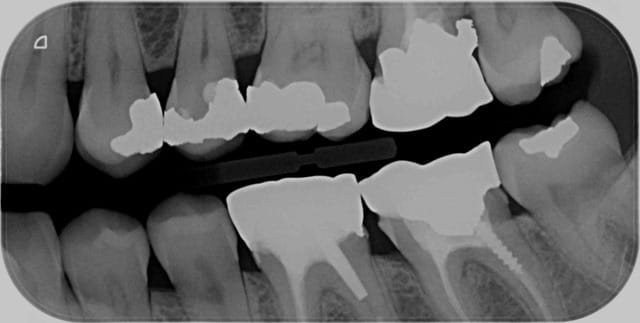

Bon alors on compte quoi là ? -)

Problème de centre sur les 3 et les 4 pas facile de déterminer le centre du secteur. -)

Plus facile de déterminer le centre du secteur sur les molaires par contre. -)

J'ai dénombré 8 secteur les quels ? -)

Capture d e cran 2016 02 17 09.36 - Eugenol

Et ca ?

2 secteurs : 36 35 et 35 34 33

ou un secteur 36,35,34 hein ? -)

Par ce qu'en fait c'est centré sur 36 et 34 . -)